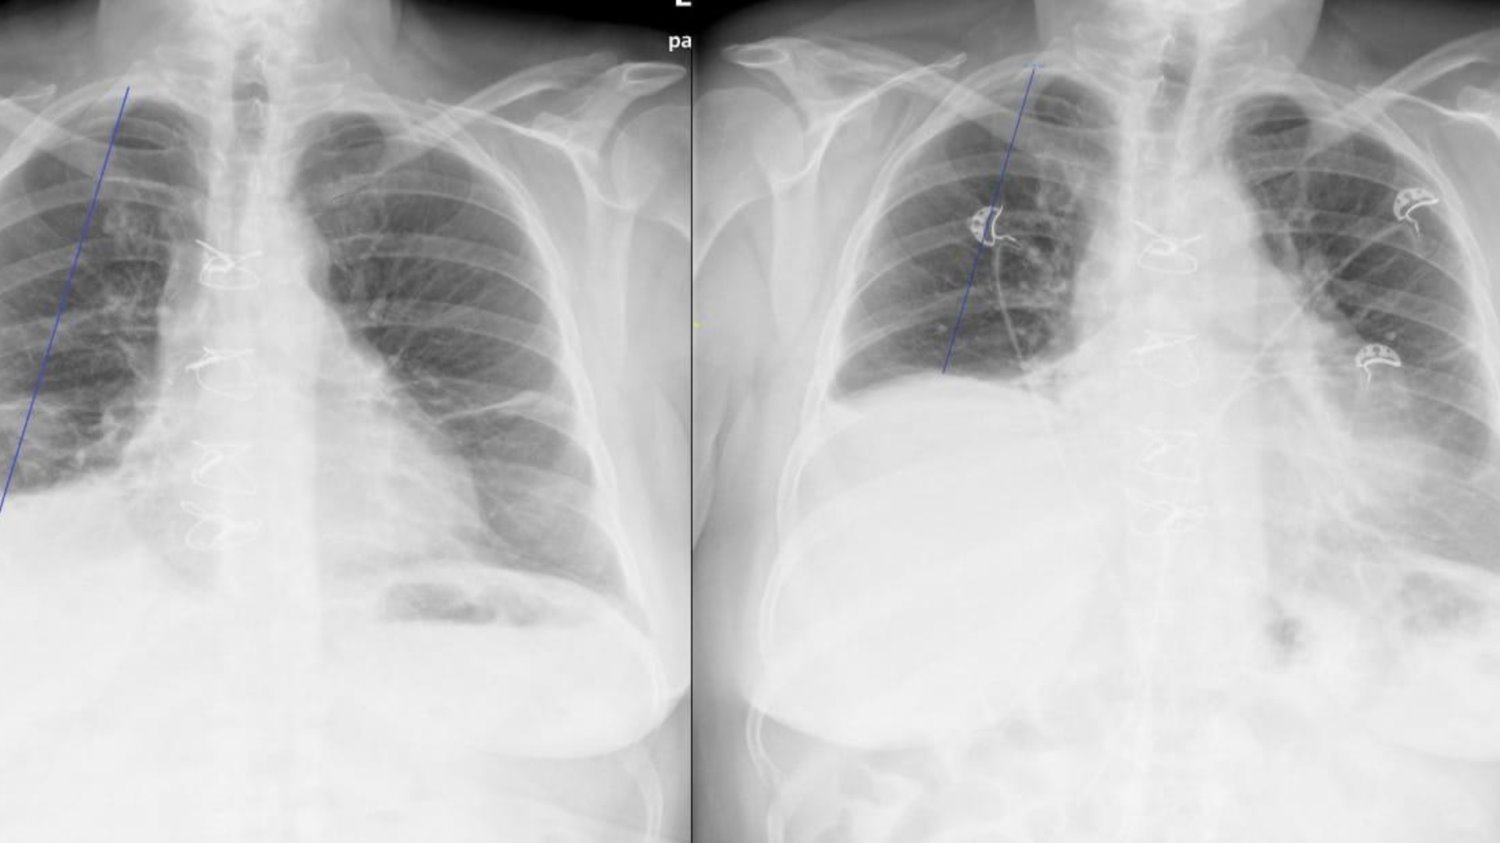

בתמונה: מימין, לפני הניתוח הסרעפת הימנית גבוהה ולאחר הניתוח משמאל הסרעפת במצב תקין